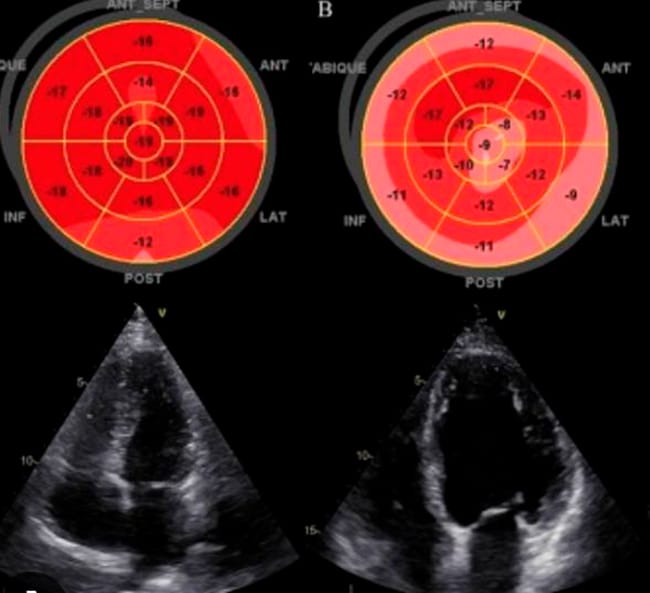

Pero si mantenemos el hábito en el tiempo, si el ejercicio se vuelve regular, empiezan a aparecer cambios estructurales sobre las cavidades del corazón. Esto es lo que conocemos como remodelado cardíaco.

El corazón, especialmente el ventrículo izquierdo, que es el principal encargado de bombear sangre al cuerpo, empieza a adaptarse al flujo constante de sangre que recibe, y a las demandas que le exiges. Las cavidades se dilatan de forma controlada, permitiendo que entre más sangre en cada latido, y, al mismo tiempo, el músculo se refuerza para bombearese volumen adicional sin perder flexibilidad.

El resultado es un corazón más grande, sí, pero sobre todo más eficiente.

Este matiz es importante. Estas adaptaciones, que son fisiológicas, en ocasiones pueden parecerse a enfermedades del corazón. Un corazón grande puede ser normal en un deportista… o un signo de patología en otro contexto.

Por eso, incluso hoy, sigue existiendo debate científico sobre dónde está exactamente el límite entre adaptación saludable y cambio potencialmente problemático.

Y esto, en medicina, no es un detalle menor. Piensa que uno requiere tratamiento, y otro no. Y así, no se trata de que el corazón cambie, sino de cómo cambia.